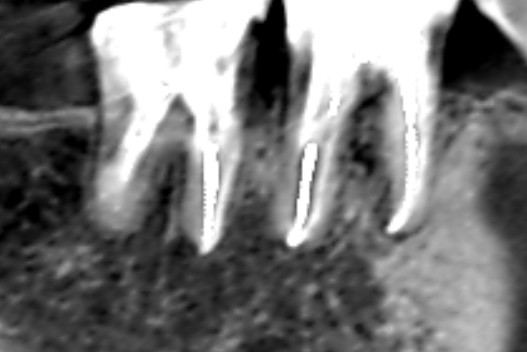

第一大臼歯と第二大臼歯の精密再根管治療後の画像です。根尖までしっかりMTAセメントで根管充填できています。